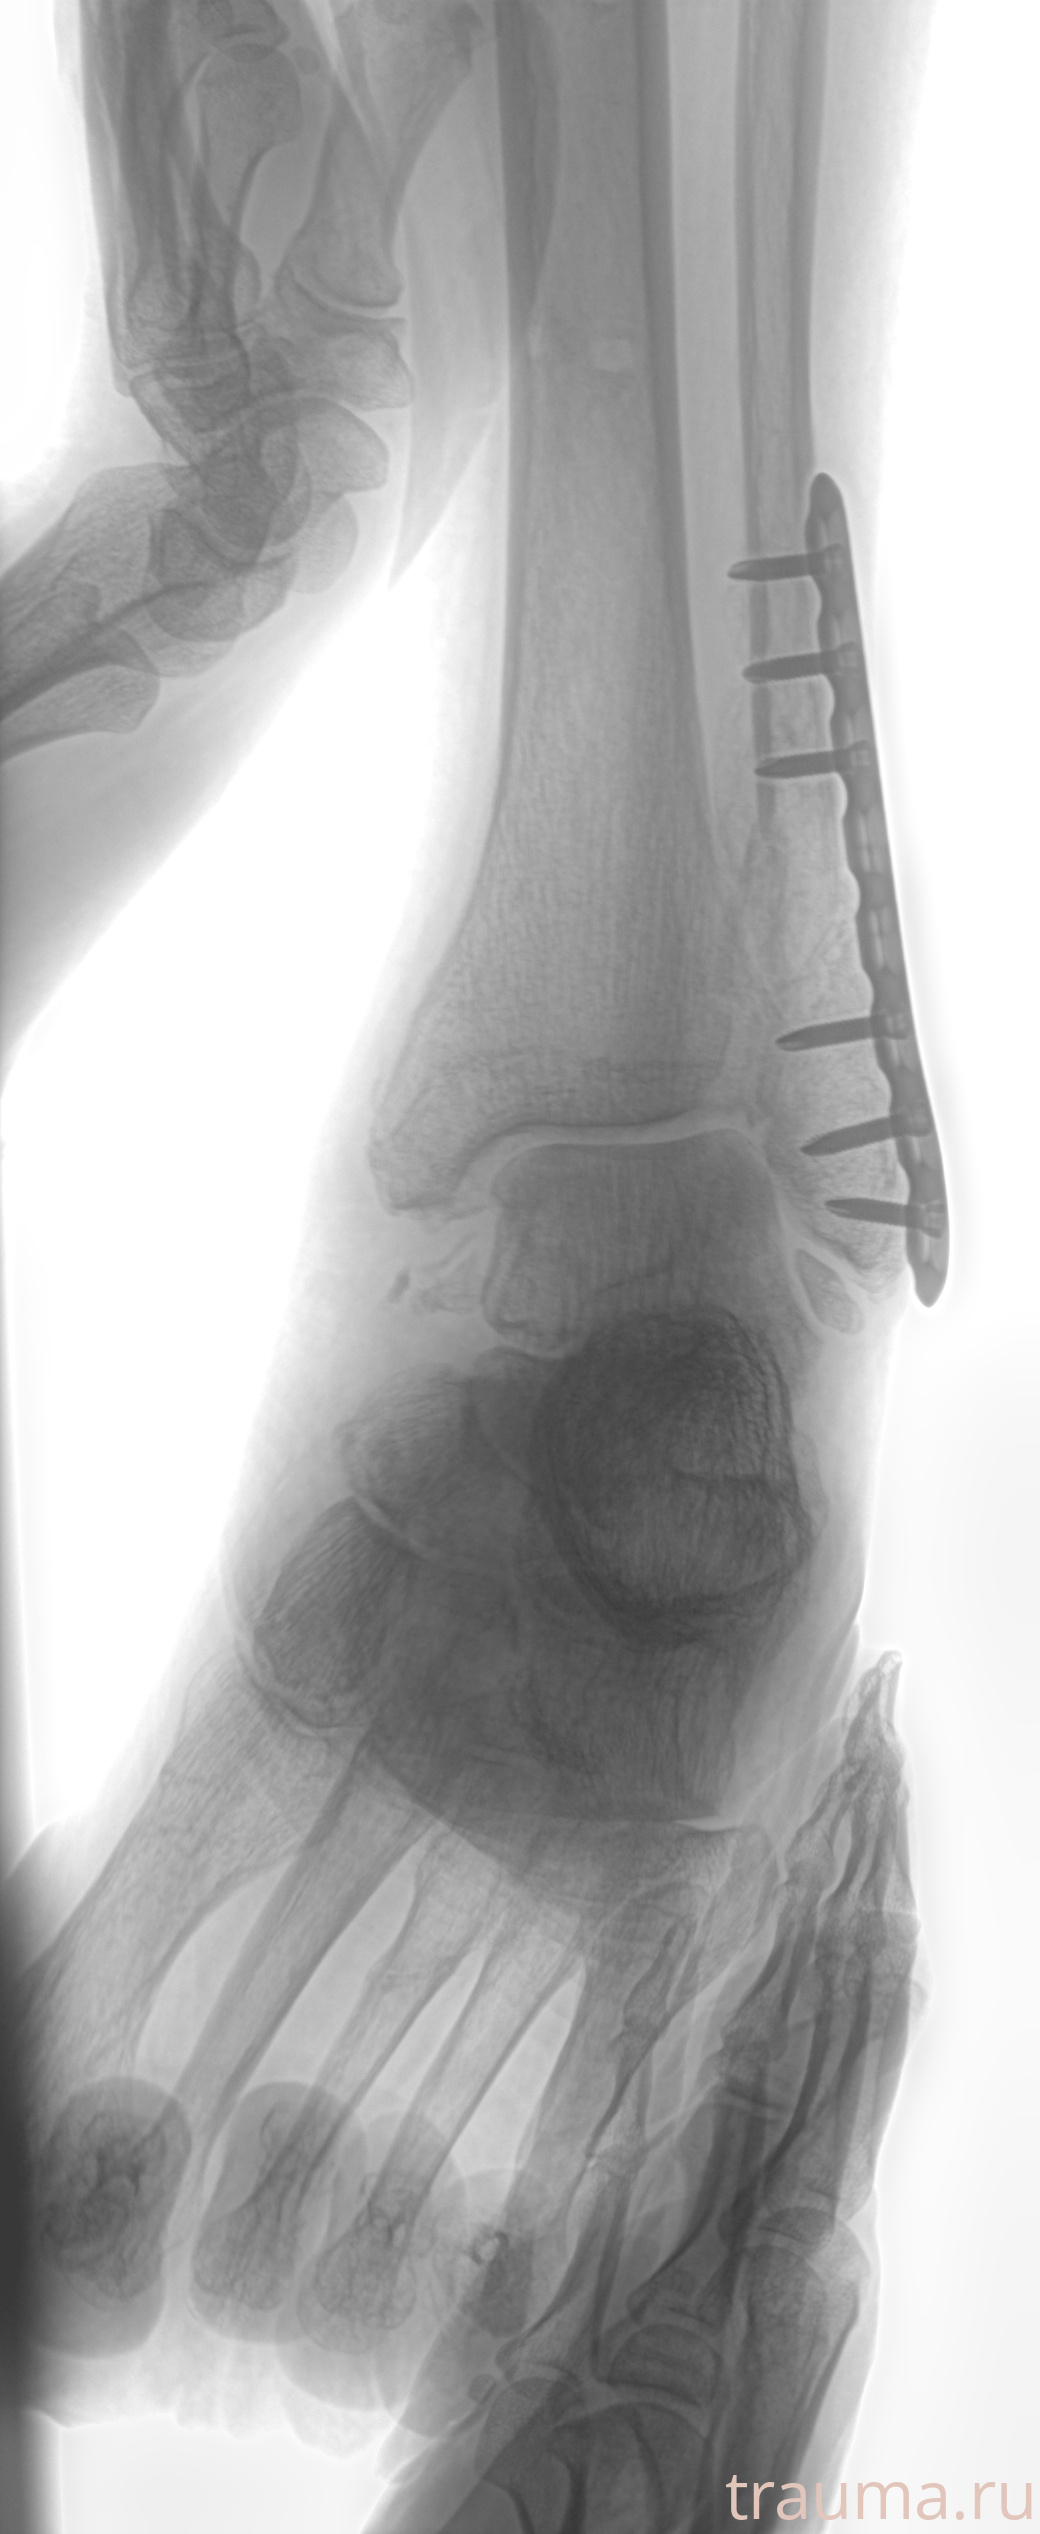

Рентгенограммы